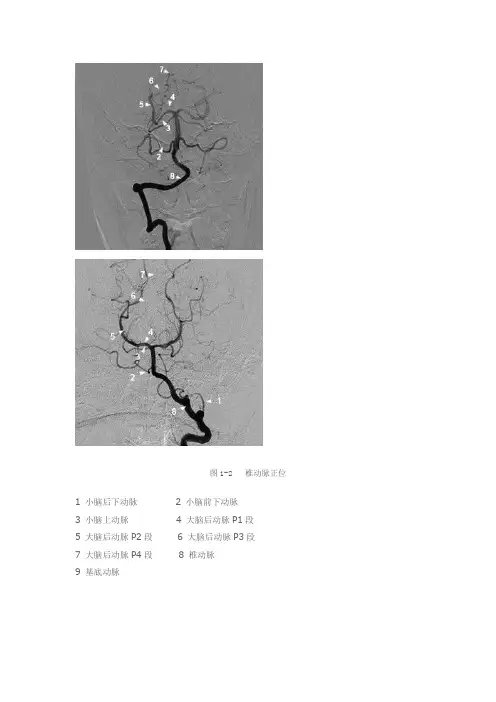

图1-2 椎动脉正位1 小脑后下动脉2 小脑前下动脉3 小脑上动脉4 大脑后动脉P1段5 大脑后动脉P2段6 大脑后动脉P3段7 大脑后动脉P4段8 椎动脉9 基底动脉图3-4 椎动脉侧位1 小脑后下动脉瘤2a 小脑前下动脉和小脑后下动脉共干(2b小脑前下动脉)3 小脑上动脉4 大脑后动脉P1段5 大脑后动脉P2段6 大脑后动脉P3段7 大脑后动脉P4段8 椎动脉9 基底动脉 10 小脑后下动脉延髓前段11 小脑后下动脉延髓外侧段12 小脑后下动脉延髓后段13 小脑后下动脉扁桃体上段正常血管造影解剖椎动脉多数起源于锁骨下动脉,两侧椎动脉的管径可以变化很大,一般情况下左侧椎动脉管径大于右侧椎动脉管径,但约1/4的正常人右椎动脉管径大于左侧椎动脉管径。